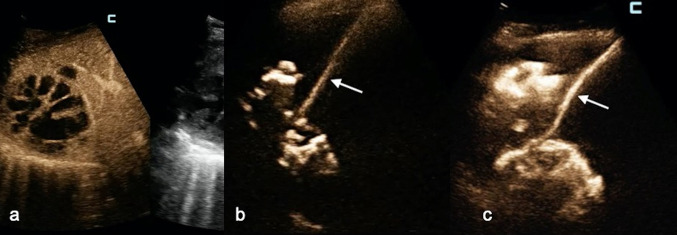

Fig. 3.

a A large abscess (between black arrows) was displayed in the middle abdomen in an 81-year-old man with high-grade fever. b After catheter placement, fecaloid material was aspirated; immediate IC-CEUS showed a fistulous communication (black arrow) between the abscess (black asterisk), and an adjacent bowel loop (b). This finding was confirmed at emergency surgery

Demonstration of communication with adjacent structures. In one patient, UCA passed from an abdominal abscess into a nearby bowel loop, prompting immediate surgery (Fig. 3). In two PLAs, IC-CEUS showed communication with an apparently unobstructed biliary tree. In this case, not only was the etiology of PLA clarified, but endoscopic stenting was also thereafter programmed. In another patient with malignant obstruction of the common bile duct and two distinct PLAs, IC-CEUS enabled visualization of fistulous communications with the right pleural space and the biliary tree (Fig. 4). Thoracic drainage and replacement of the biliary endoprosthesis were carried out, along with deployment of two catheters to drain the PLAs.